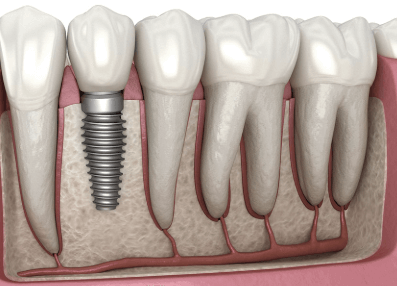

임플란트 수술 후 주의사항

- 출혈 및 부기 관리 : 수술 후 24시간 동안 얼음찜질을 하면 부기를 줄일 수 있습니다. 거즈를 2~3시간 꽉 물고 있어야 하며, 침을 뱉거나 빨아들이지 마세요.

- 음식 섭취 : 첫 24시간 동안 부드러운 음식(죽, 스프)을 섭취하세요. 뜨거운 음식과 자극적인 음식(매운 음식, 탄산음료)은 피해야 합니다. 2주간 단단한 음식(견과류, 오징어 등)은 피하는 것이 좋습니다.

- 구강 위생 관리 : 첫날은 칫솔질을 하지 말고, 이틀째부터 부드러운 칫솔로 양치하세요. 소독용 가글(클로르헥시딘)로 가볍게 헹구세요.

- 운동 및 생활 습관 : 격렬한 운동은 최소 1주일간 금지하세요. 흡연과 음주는 최소 2주간 금지, 가능하면 3개월 동안 피하는 것이 좋습니다. 잘 때는 머리를 약간 높여서 출혈과 부기를 예방하세요.